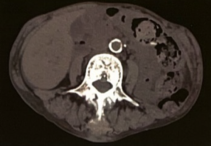

(3)恶性肿瘤:患者有多处肿块且疼痛明显,恶性肿瘤需予以鉴别,包括淋巴瘤、多发性骨髓瘤等,但本患者检验未见肿瘤标志物升高,免疫固定电泳未见单克隆,且既往曾多次臀部及肩部有类似肿块切除后病理均提示淀粉样变,故不考虑该诊断。

全身骨痛是透析相关淀粉样变患者常见的症状之一,其疼痛程度和持续时间因个体差异而异。这种疼痛可能源于β2-MG在骨骼中的沉积,导致骨骼结构的改变和功能的受损。此外,长期的透析治疗也可能导致电解质代谢紊乱、钙磷代谢失调等问题,进一步加剧骨骼疼痛。腕管综合征多为DRA的早期临床表现,主要由β2-MG淀粉样物质沉积于腕管内的腱鞘、滑膜、屈肌腱或屈肌韧带,造成腕管腔相对狭小、腕管压力增高,正中神经受压所致。临床表现为患肢桡侧半手指麻木或刺痛,夜间明显,活动后可减轻;病情严重者大鱼际肌萎缩和功能障碍;屈腕试验,神经叩击试验,或指压试验可阳性。囊性骨损害是DRA最常见的临床骨损害,常发生在腕骨、肱骨头、股骨颈、髋臼、胫骨平台等。囊肿数量和大小随透析龄的延长而增加。囊性骨损害为多发性、对称性软骨下溶骨性改变。淀粉样骨关节病绝大多数发生于滑膜关节附近,并常累及邻近关节囊和韧带,肩关节是最常见的受累部位。破坏性脊柱关节病变主要累及颈椎,是DRA的一种致残性并发症,常为多发性、发展迅速的椎间隙变窄,伴有邻近椎板受侵蚀致骨质破坏。对于出现全身骨痛的患者,医生应高度警惕透析相关淀粉样变的可能性。除了详细的病史询问和体格检查外,还需要进行相关的实验室检查,如血清β2-MG水平的测定,以及影像学检查,如X线、CT或MRI等,以明确是否存在骨骼的病变。

临床上加强对维持性血液透析患者DRA的重视。血清β2-MG及其清除率的动态监测,临床症状的观察、及时的B超、CT及MRI检查是十分必要的。